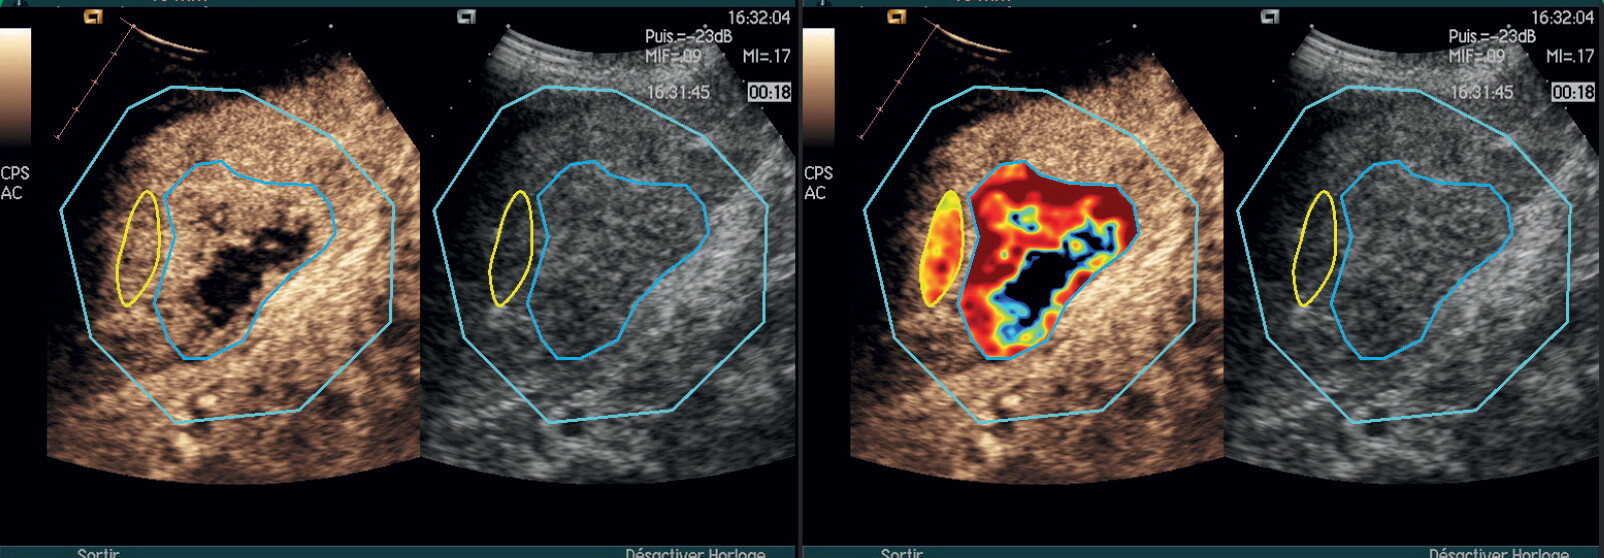

VueBox® Research is a general-purpose software for quantifying tissue perfusion using Dynamic Contrast-Enhanced Ultrasound (DCE-US).

VueBox® Research provides a set of technical functionalities enabling the analysis of DICOM clips obtained with a wide range of ultrasound systems.

Its unique Bracco-patented technology and linearization process allow quantitative assessment of tissue perfusion after bolus injection or infusion.

• Multiple parametric images